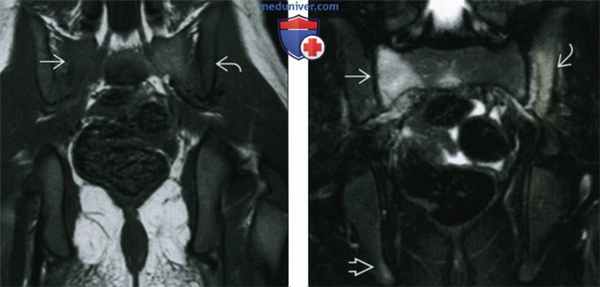

(Слева) Фронтальная Т1 ВИ МР-И десятилетнего пациента: небольшие изменения, заключающиеся в ↓ интенсивности сигнала в крыле крестца справа и задней части крыла подвздошной кости. Иногда сложно определить ↓ сигнала в режиме Т1 у детей, так как большая часть их костного мозга еще не замещена жировой тканью.

(Справа) Фронтальное Т2ВИ FS МР-И, этот же пациент: визуализируется ↑ интенсивности сигнала в коаном мозге крыла крестца справа, задней части крыла подвздошной кости слева и правого седалищного бугра. У пациента нормальная рентгенограмма, сцинтиграфия и посев крови: трепанобиопсия доказала наличие хронического рецидивирующего многоочагового остеомиелита.